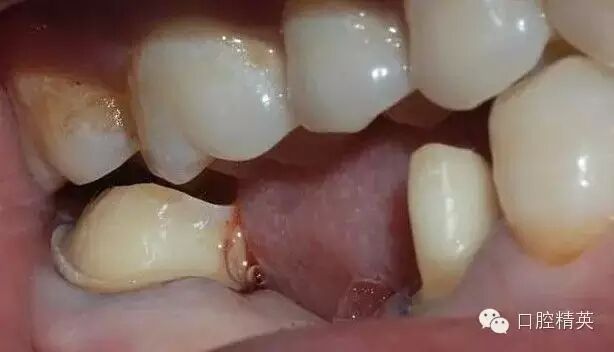

鄰面的制備,先用較細(xì)的金剛砂車(chē)針貼基牙鄰面制備,勿損傷鄰牙

鄰面制備完成后